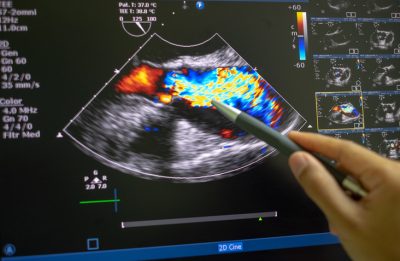

Synopsis: A UK National Health Service database study of stress echocardiography has shown the degree of ischemia accurately predicts the risk of future cardiovascular events over five years. The same study also showed that a negative test in patients without a history of cardiac disease identifies patients with no more than the expected background risk of an event for patients in this demographic for five years.

The Echocardiography: Value and Accuracy at Rest and Stress (EVAREST) study includes data from the British Society of Echocardiography National Review of Stress Echocardiography Practice (BSE-NSTEP), a multicenter, observational study of the use, performance, and accuracy of stress echocardiography in real-world practice in 32 National Health Service (NHS) hospitals in the United Kingdom.

Stress echocardiography was performed according to the individual hospital protocols, as was patient management. Long-term follow-up data were obtained from the NHS in patients who consented to a 10-year follow-up.

After excluding patients with incomplete data, 5,503 patients who had a median follow-up duration of 829 days (median age 66 years, 59% men) were enrolled. Dobutamine stress was the most common (64%), then exercise (treadmill 28%, bicycle ergometer 7%), then pacemaker (< 1%). Also, atropine (29%) and echo contrast (79%) were frequently given. Resting wall motion abnormalities were present in 14% of the studies and were significantly associated with positive tests (odds ratio, 3.95; 95% confidence interval [CI], 3.27-4.77; P < 0.001).

During follow-up, in those with a positive stress echo 6% died and in those with a negative stress echo 4% died. Cardiac death occurred in < 1.0% of those with a negative stress echo and in 2% of those with a positive stress test.

Although there was a significant association between positive tests and all-cause and cardiac deaths, if other risk factors were considered on multivariable analysis, this significance was lost. However, on multivariable analysis, a positive test was associated with myocardial infarction (MI) (hazard ratio, 2.71; 95% CI, 1.73-4.24; P < 0.001) and this association was stronger the more left ventricular (LV) wall segments were abnormal with stress.

The event-free survival curve for a negative stress test showed a < 1% rate of MI or death per year in those with no prior history of coronary artery disease (CAD), which translates to < 5% at five years, which is similar to the background risk rate in this demographic.

In those with a history of prior CAD, a negative stress test is associated with a 1.5% per year rate of death or MI, and the curve rose above 5% at four years. The authors concluded that in a real-world practice setting, the degree of ischemia on stress echo accurately predicts the risk of future cardiovascular (CV) events over five years and a negative stress echo in patients without known CAD predicts a risk of CV events at a rate no higher than the background rate for five years.